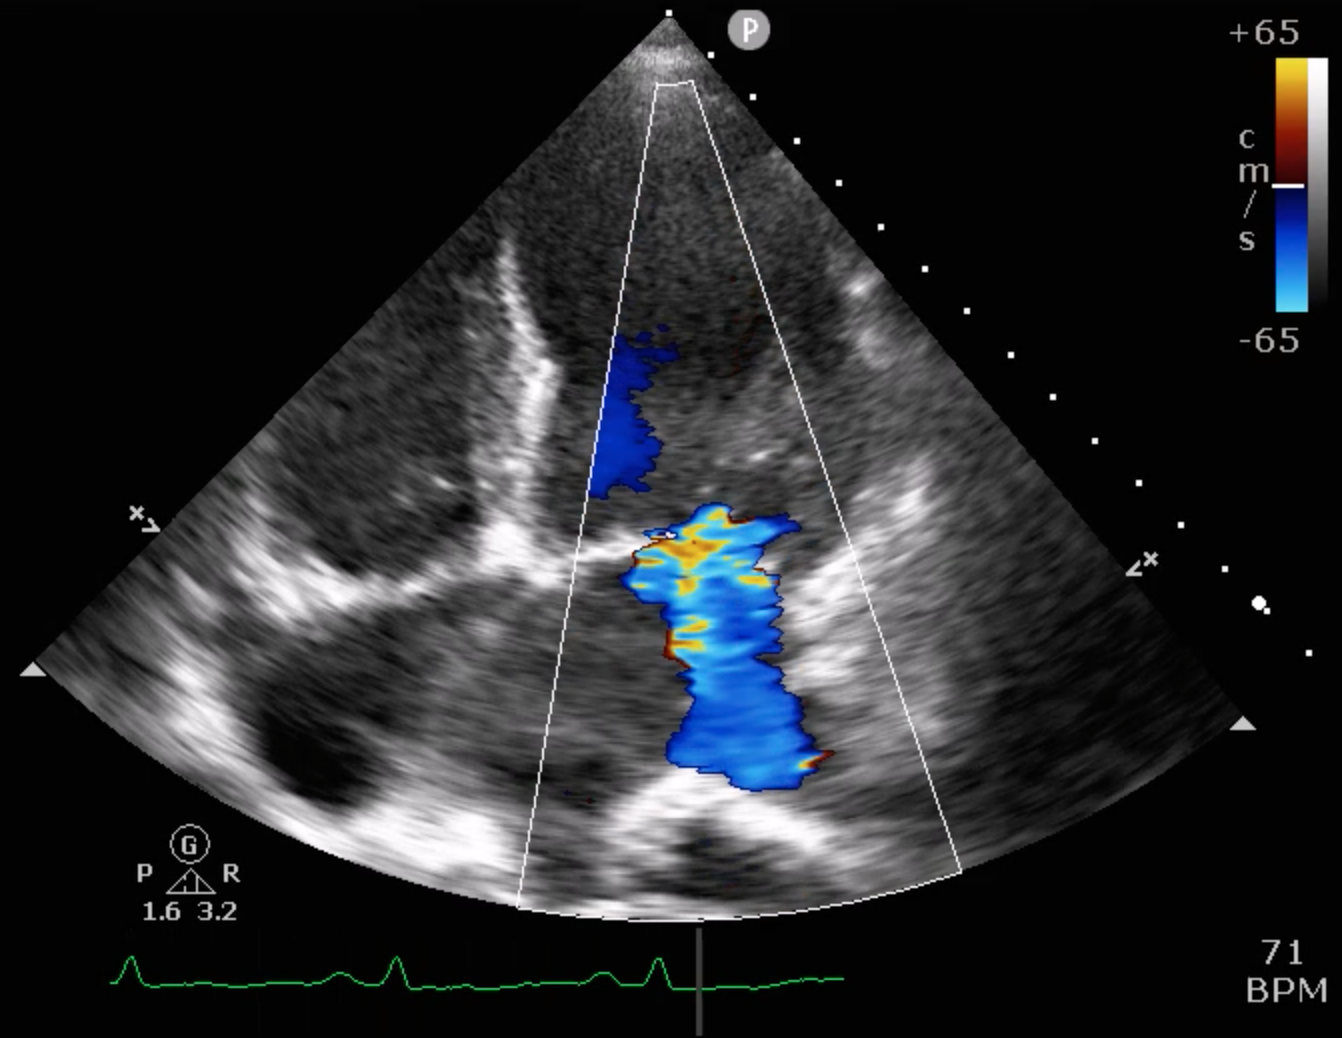

Relevant Test Results Prior to Catheterization

Echocardiography showed severely reduced LV systolic function with an EF around 20%, global hypokinesia, and anterior septal hypokinesia. Severe mitral regurgitation with left atrial enlargement was noted. Mild RV dysfunction was present, and Doppler suggested elevated filling pressures. These findings were obtained prior to catheterization.